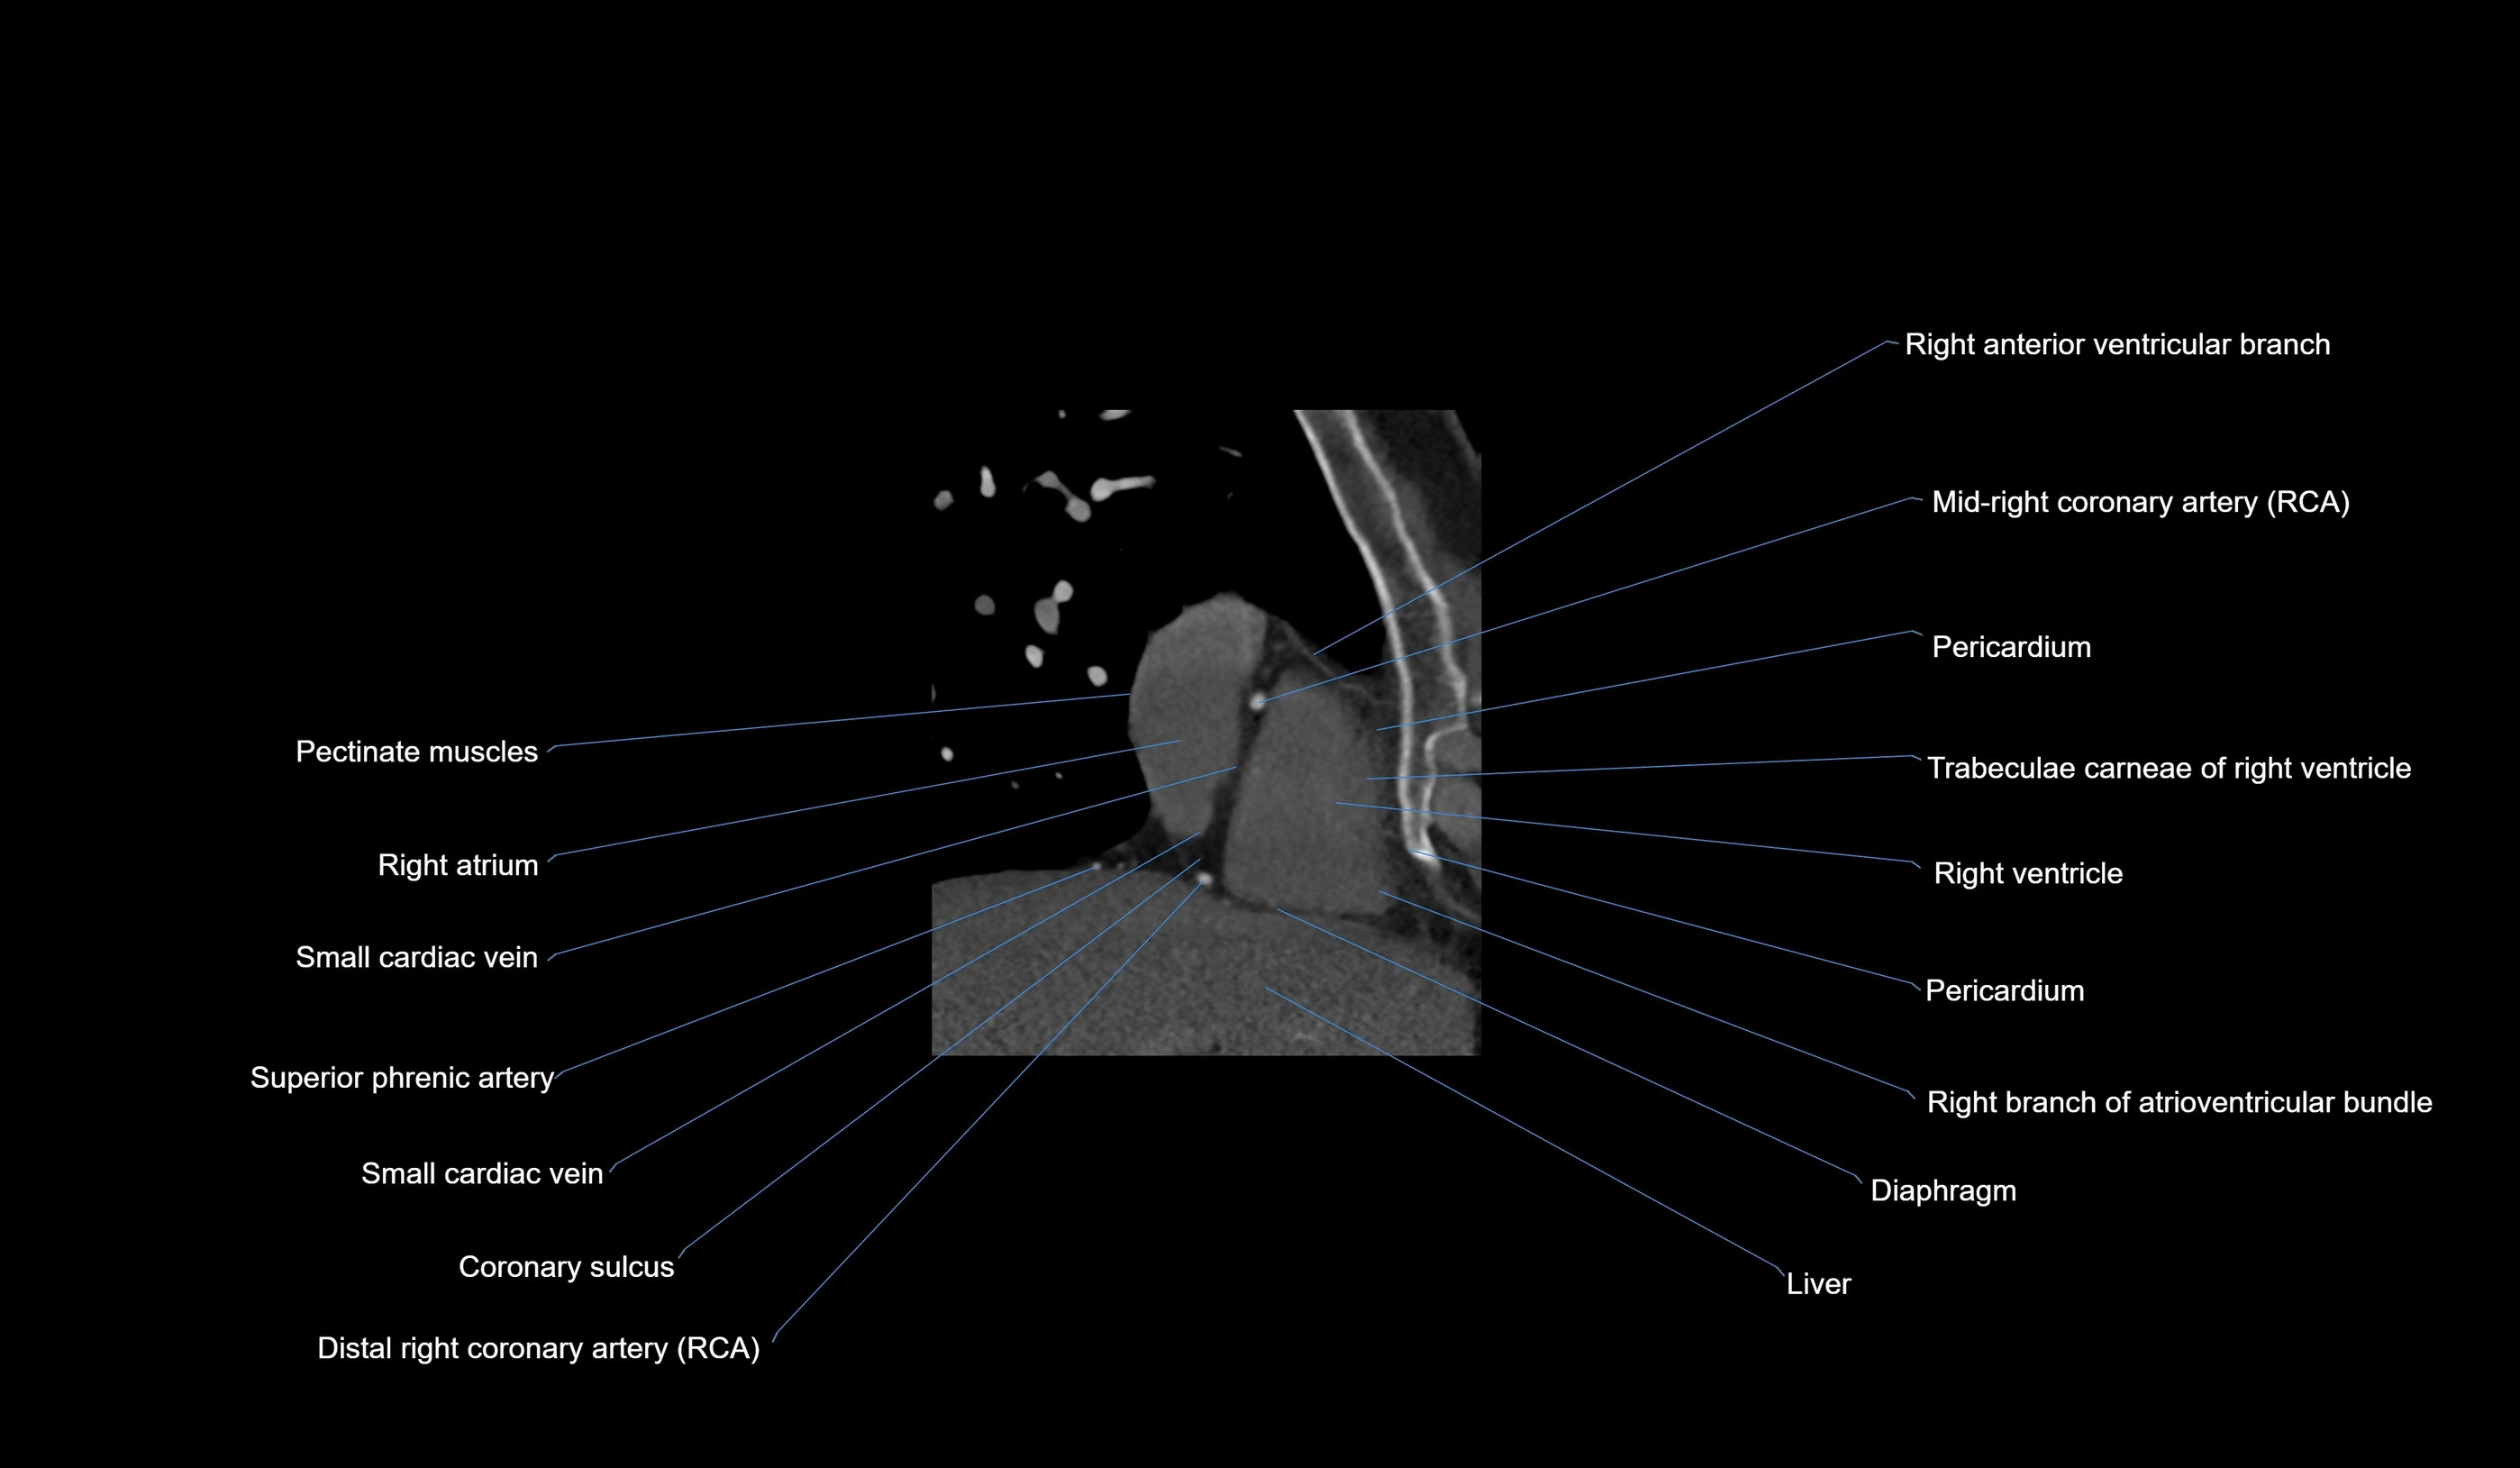

- Right coronary artery (RCA)

- Right atrium

- Right ventricle

- Pectinate muscles

- Small cardiac vein

- Coronary sulcus

- Right posterior descending coronary artery (Right PDA)

- Right branch of atrioventricular bundle

- Pericardium

- Diaphragm

- Acute marginal artery (AM)